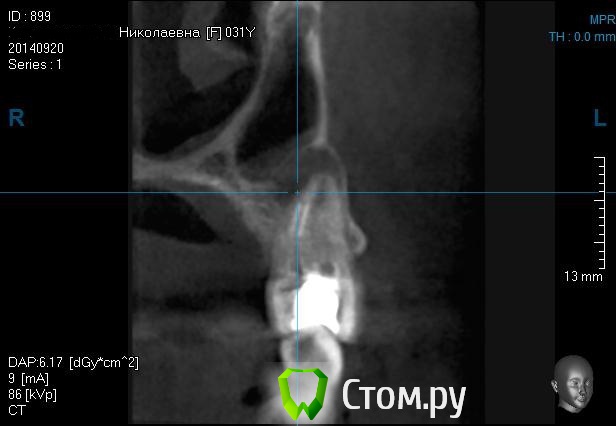

BORA Опубликовано 11 ноября, 2013 Поделиться Опубликовано 11 ноября, 2013 (изменено) Добавлю к теме случай:http://s57.radikal.ru/i156/1311/8f/f528f9ef3914.jpgпопробую vip-ctКак думаете,кисту не трогать- зашить?(jpg что то сохранил в паинте мелким,подскажите как увеличить?..спасибо) Изменено 11 ноября, 2013 пользователем BORA Ссылка на комментарий

kriokov Опубликовано 12 ноября, 2013 Поделиться Опубликовано 12 ноября, 2013 (изменено) Зачем тут подключать лора?на скрине не совсем четко видно, что в пазухе. Убрать зуб, кисту, закрыть сообщение. Через 1-2 мес кт сделать там и определиться с лором.И еще. Не факт , что перфорация будет. Иногда тонкий слой кортикального купола на кт не видно, но паца лучше заранее подготовить. Изменено 12 ноября, 2013 пользователем kriokov 4 Ссылка на комментарий

sergio Опубликовано 13 ноября, 2013 Поделиться Опубликовано 13 ноября, 2013 2 этапом после удаления,после устранения инфекции,повторное к/т.может гайморотомия в ЧЛХ.ЛОР здесь ни при чем,там одонтогенный гайморит,хотя данное к/т не особо информативно-про снята только бухта..только второй раз сделайте к/т 15 на 15, полностью придаточные пазухи.а то у вас там видно только бухту Ссылка на комментарий

Kostoprav Опубликовано 3 октября, 2014 Поделиться Опубликовано 3 октября, 2014 (изменено) убрал зуб, убрал оболочку( перфы слава Богу не обнаружил хотя по кт можно заподозрить) промыл бетадином и кинул на всякий пожарный полнослойный, ротированый лоскут с неба.так уже не первый раз- на кт полость кисты соединена с пазухой , а в реале тонкая, замыкающая, костная пластинка все же есть) Изменено 3 октября, 2014 пользователем Kostoprav Ссылка на комментарий

kriokov Опубликовано 3 октября, 2014 Поделиться Опубликовано 3 октября, 2014 кт полость кисты соединена с пазухой , а в реале тонкая, замыкающая, костная пластинка все же есть) пластинка тоньше , чем разрешающая способность кт, наверное поэтому и выглядит как сообщение с пазухой. Действительно часто такое. 1 Ссылка на комментарий